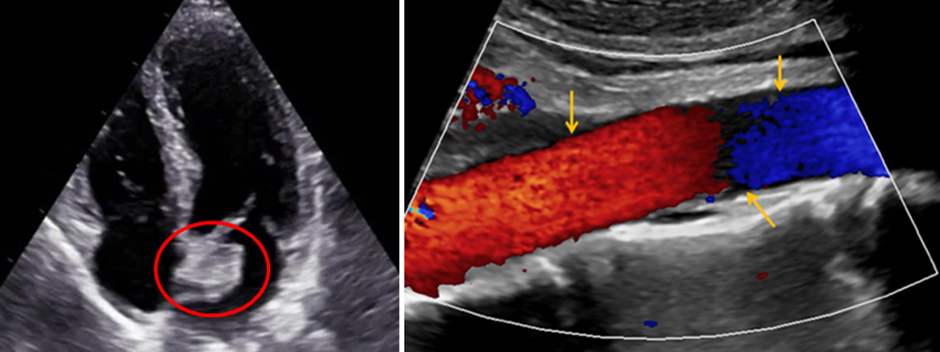

A. Cardiac Imaging (to detect the myxoma):

• Transthoracic or Transesophageal Echocardiography:

• Mobile, echogenic mass attached to the interatrial septum (left atrial side)

• Pedunculated, often prolapses into the mitral valve orifice

B. Vascular Imaging:

• Duplex ultrasound: May help identify absent flow in distal vessels